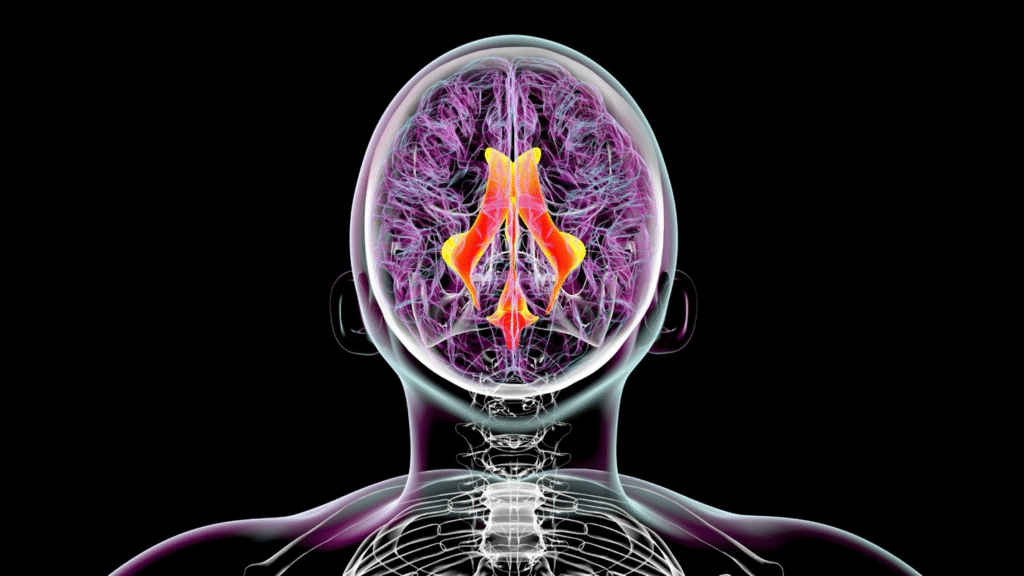

Alzheimer’s Brains Struggle to Remove Waste

Ventricles (red/yellow) are cavities filled with a fluid that flows throughout and around the brain to remove waste. Alzheimer’s impairs this process, allowing toxic proteins to build up.